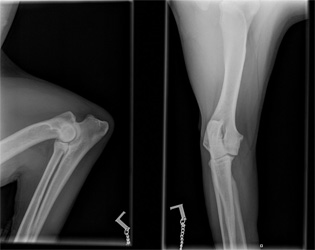

Norpan kinnerten ja kyynärten röntgenkuvat

Norpan jalkavaivoista tai yleensä OCD:sta kiinnostuneet voivat vilkaista alla olevia kuvia. Kuvat on otettu ajalta ennen kinnerten tähystystä ja ne saa suuremmaksi klikkaamalla. Lisäsin linkkien takaa löytyviin kinnerkuviin muutamia huomioita, jotka jäivät Esa Eskeliseltä ja Kai Skutnabbilta haetuista lausunnoista mieleen. En osaa itse tulkita röntgenkuvia, joten toivottavasti muistini ei reistaillut noita yksityiskohtia merkkaillessa. Kyynärkuvista jätin huomiot pois, koska en osaa osoittaa vasemmasta kyynärästä riittävän tarkasti sitä kohtaa, jossa Skutin mukaan on vähäisiä reaktioita havaittavissa. Eskelinen suositteli lausunnossaan myös kyynärnivelten tähystämistä, mutta Skutin mukaan oikea kyynärnivel on puhdas eivätkä vasemmankaan reaktiot viittaa OCD:hen.

Kyynärnivelet